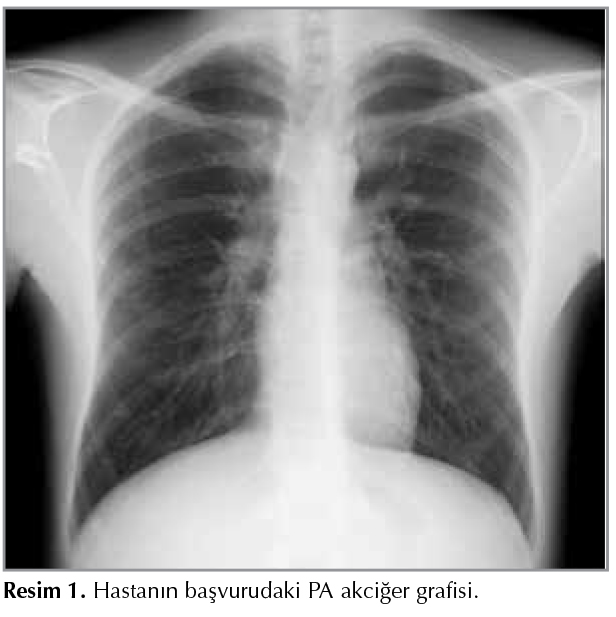

Otuz beş yaşında erkek hasta bir aydır halsizlik, eklem ağrıları, ara ara olan ateş y?ksekliği, iştahsızlık, 1 ay i?inde 10 kilo kaybı ve gece terlemesi yakınmaları ile kurumumuza başvurdu. Solunumsal yakınması olmayan hastanın dinlemekle akciğer sesleri normaldi, yapılan sistemik muayenesinde boyun sağ lojda yaklaşık 1 cm boyutunda ağrılı, mobil lenf nodu saptandı. ?zge?mişinde bilinen kronik bir hastalığı olmadığı, 17 paket/yılı sigara kullanımı olduğu; soy ge?mişinde ise teyzesinde meme kanseri olduğu ?ğrenildi. Genel durumu iyi, bilinci a?ık, oryante ve koopere idi. PA akciğer grafisinde total vertikal uzunluk artmış, her iki kostodiyafragmatik sin?sler a?ık olup sağ hilus hafif dolgun g?r?n?mde idi (Resim 1). ?ekilen boyun tomografisinde her iki submandibuler bez komşuluğunda, her iki ?n?arka juguler zincirde yaklaşık 11 x 10 mm boyutlara ulaşan round konfig?rasyonlarda birka? adet lenf nodu ve toraks bilgisayarlı tomografi (BT)'de mediastinal 1, 2, 4R-L, 7 nolu istasyonlarda b?y?ğ? 4R'de 18 x 17 mm boyutunda multipl lenf nodları saptanan hastanın ayırıcı tanısı i?in tetkikleri istendi (Resim 2). Bu arada tetkikleri devam eden hastaya seftriakson, klaritromisin ve antiinflamatuvar tedaviler başlandı. ?nceden de ateşli olduğu d?nemlerde parasetamol preparatları ve antibiyoterapi k?rleri aldığını ifade eden hastanın genel v?cut kırgınlığı ve halsizliğinin devam ettiği sorgulamadan ?ğrenildi.

Resim 1